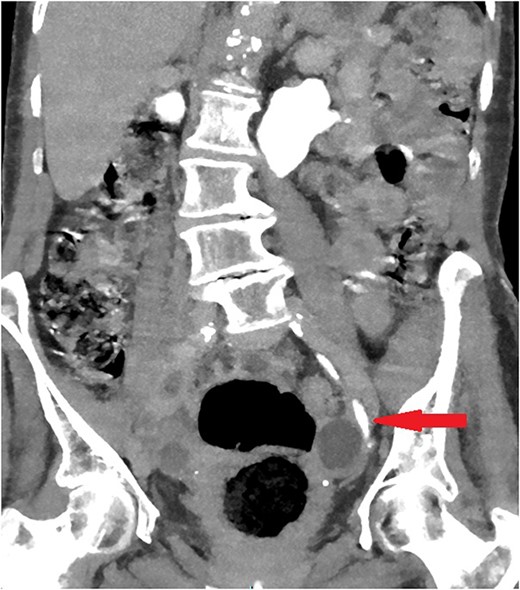

On examination, the patient was feverish (temp 38.2) and had left sided abdominal pain without tenderness on palpation. Her blood investigations did not show any significant changes. Initial washout through the catheter increased the pain and it showed passive drainage only. Non-contrast computed tomography (CT) was performed to assess the catheter position. Surprisingly, the catheter was passing into the left ureter with the catheter balloon inflated in the mid-ureter (Fig. 1).

Coronal section of abdomen and pelvis non-contrast CT: The urethral catheter migrates into the left ureter up to the mid-ureter.